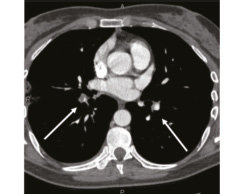

В 1993 г. на основании характерных признаков электрокардиограммы (ЭКГ) при профилактическом обследовании диагностирован феномен Вольфа–Паркинсона–Уайта. Клинических проявлений, снижающих качество жизни, пациентка не отмечала. К врачам далее не обращалась. В связи с появлением в 2015 г. одышки, перебоев в работе сердца, сердцебиения наблюдалась у участкового терапевта с диагнозом: ишемическая болезнь сердца, гипертоническая болезнь. Эхокардиография (ЭхоКГ), нагрузочные тесты не проводились. На фоне приема лозартана 25 мг/сут достигнуты целевые значения АД. В январе 2017 г. в связи с зарегистрированным на ЭКГ пароксизмом тахикардии с узкими комплексами QRS пациентка в порядке скорой помощи поступила с диагнозом «пароксизмальная суправентрикулярная тахикардия» в ЦРБ, где ритм был медикаментозно восстановлен. Далее в краевой больнице проведено внутрисердечное электрофизиологическое исследование и по его результатам – радиочастотная аблация дополнительных проводящих путей. Послеоперационный период протекал без осложнений. Однако в июне 2017 г. вновь появилась одышка при выполнении привычного объема физической нагрузки. По данным ЭКГ и рентгенограммы органов грудной клетки патологии не выявлено. Вскоре появилось кровохарканье (в течение 3 дней), и пациентка была направлена к фтизиатру, которым исключен туберкулез легких. 27.07.2017 на фоне значительного усиления одышки, выраженной тахикардии она потеряла сознание и в порядке скорой помощи доставлена в дежурный стационар, где травматологом и неврологом исключены сотрясение головного мозга и закрытая черепно-мозговая травма. Пациентка отпущена домой. В связи с сохраняющейся одышкой при подъеме на один лестничный пролет в августе 2017 г. по собственной инициативе она обратилась к кардиологу. При проведении ЭхоКГ выявлены увеличение правых камер сердца и признаки их объемной перегрузки. С предварительным диагнозом ТЭЛА пациентка направлена в дежурный стационар, где в экстренном порядке проведена спиральная компьютерная томография (СКТ) с контрастированием легочной артерии. Выявлены признаки легочной тромбоэмболии крупных и средних ветвей легочной артерии (ЛА) с обеих сторон (рис. 1–4). При целенаправленном сборе анамнеза выяснилось, что в течение 3 лет (с 2014 г.) пациентка принимает Линдинет 20 мг – монофазный пероральный контрацептив (этинилэстрадиол + гестоден), назначенный гинекологом с целью контрацепции. По данным ультразвукового исследования вен нижних конечностей выявлен тромбоз суральных вен справа. Линдинет отменен. На фоне лечения антикоагулянтами (гепарин, эноксапарин) состояние женщины несколько улучшилось. Она переведена на варфарин, который далее заменен на апиксабан в дозе 10 мг 2 раза в день.

СКТ с контрастированием ЛА | |

14.08.2018 | 26.09.2018 |

Рис. 1: а – тромбы в верхнедолевой ветви левой ЛА; б – верхнедолевая ветвь левой ЛА проходима. | |

Рис. 2: а – тромбы в правой ЛА и нижнедолевой ветви левой ЛА; б – правая ЛА и нижнедолевая ветвь левой ЛА проходимы. | |